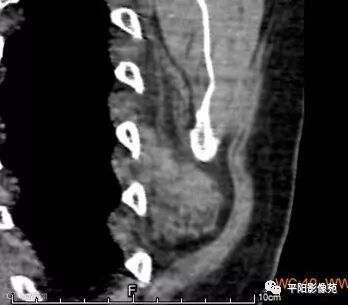

病例2

现病史: 患者约5月前无意见发现左背部一肿物,质硬,稍有活动度,疼痛不明显,无发热寒战。

影像表现

两例患者均为左侧肩胛下实性软组织肿块,边缘模糊,质软,内为肌肉样密度及脂肪密度,以肌肉样密度为主。

CT:边界模糊,与肌肉相似的密度,病变内部可见点状、条状脂肪密度,增强扫描轻度强化或无强化。